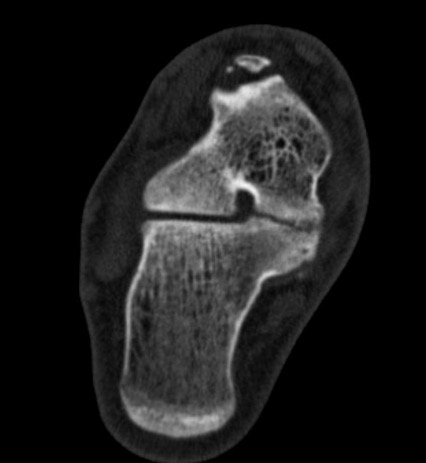

CT

TC coalition middle facet

Complete synostosis of the medial TC joint with OA of the posterior subtalar joint